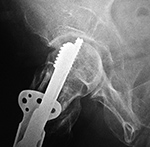

| Fixation screw projecting into right hip joint |

| The compression screw has slid distally in the barrel as it was designed to do when the femoral neck fracture site becomes compressed. This did not prevent the screw from cutting out of the femoral head (curved arrow). From Hunter, 1994 |